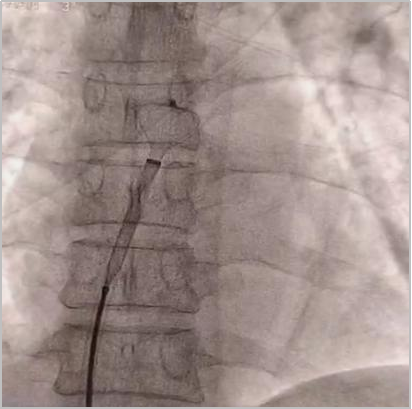

术中所见

术中测试